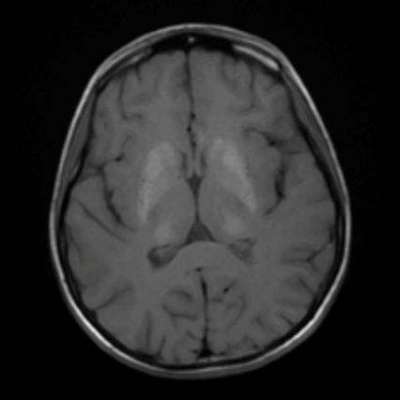

- B) Aksiyel T1A görüntülerde her iki lentiform ve kaudat nukleuslarda, talamuslarda simetrik hiperintensite (oklar) izleniyor. Bu düzeyde tariflenen sinyallerin SWI ve faz görüntülerde kalsifikasyon ile uyumlu olduğu görülmektedir (oklar). T2A görüntüde yaş ile uyumsuz serebellar atrofi ile uyumlu foliada derinleşme ve 4. ventrikül genişliğinde artış izlenmektedir (oklar).

- BT’de birden fazla lokalizasyonda multipl enfarkt benzeri odaklar ve özellikle ileri yaş hastalarda belirginleşen bazal gangliyon kalsifikasyonları izlenebilir. Lezyonlar çoğunlukla pariyeto-oksipital ve pariyeto-temporal bölgelerde yoğunlaşır ve serebral atrofi eşlik edebilir.

- MRG’de akut fazda T2/FLAIR hiperintensiteyle birlikte giral şişme ile karakterize enfarkt-benzeri lezyonlar ve subkortikal beyaz cevher tutulumu görülür. DWI’da artmış sinyal dikkat çekmekle birlikte ADC değerlerinin normal ya da hafif artmış olması, baskın sürecin vazojenik ödem olduğunu gösterir.